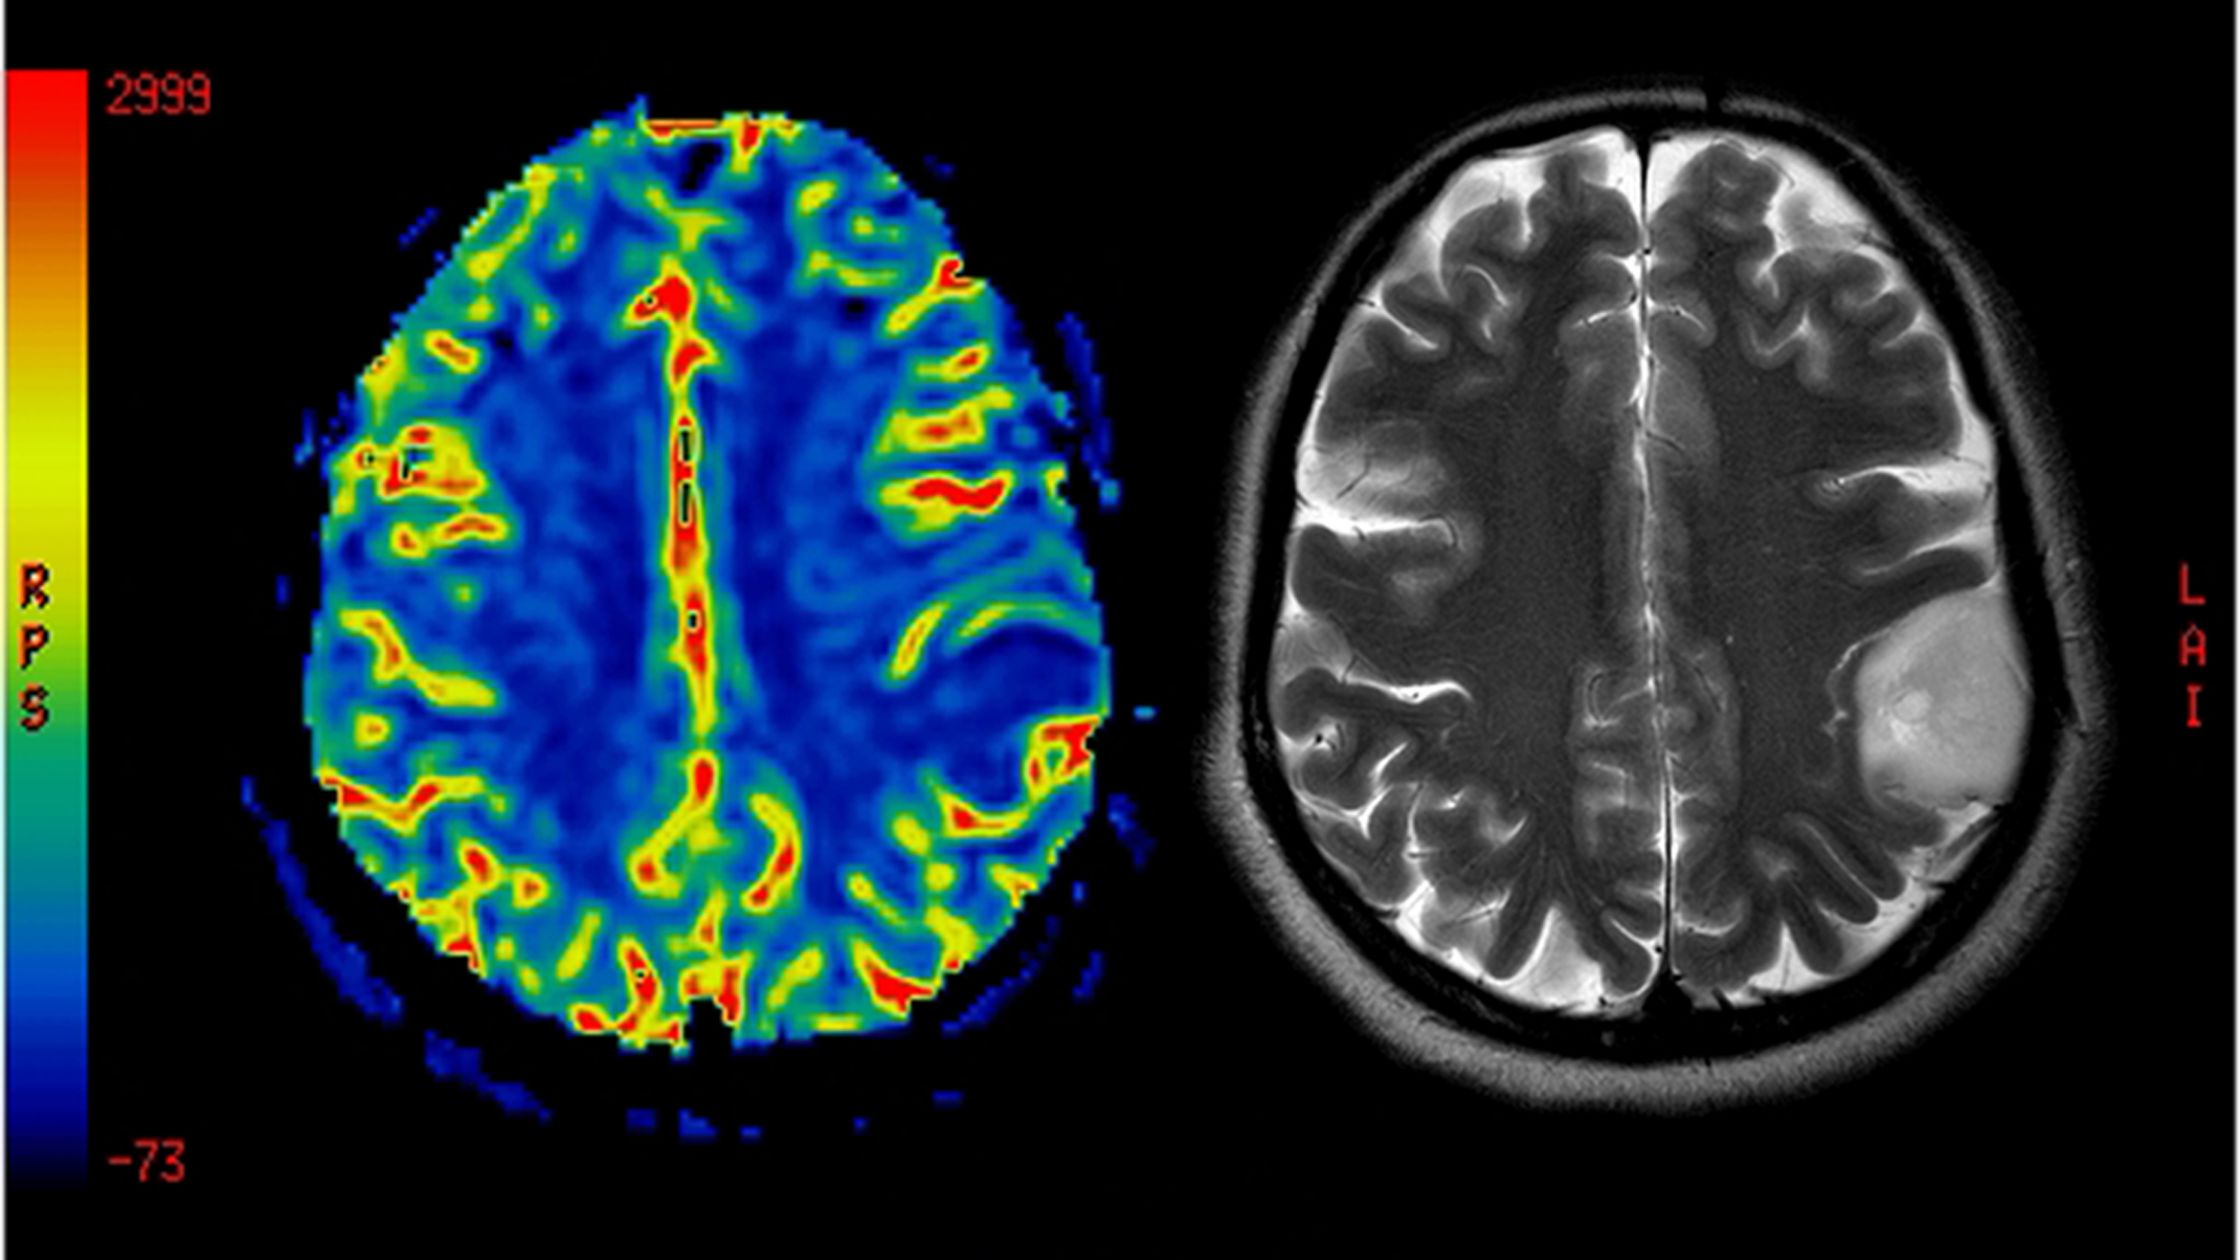

استشاري جراحة المخ والأعصاب و العمود الفقري

دكتوراة جراحة المخ و الاعصاب و العمود الفقري جامعة القاهرة

أستاذ و استشاري جراحات المخ و الاعصاب والعمود الفقري بالقصر العيني

خدمات عيادة د/إبراهيم الشال